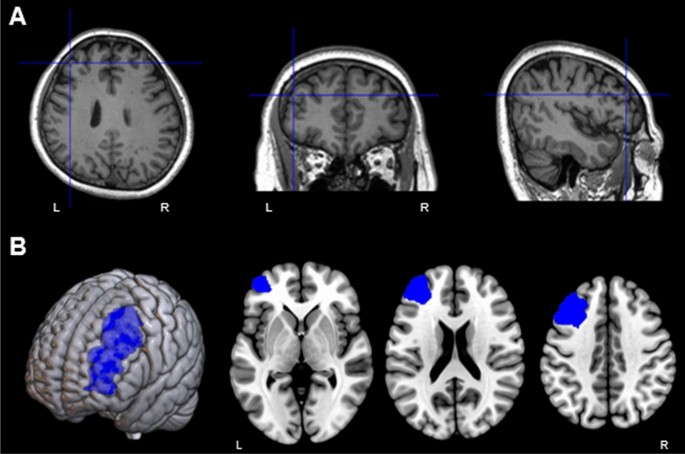

Table 2 summarizes the applied parameters for treating depression. The stimulation intensity was 100% of the individual MT. As shown in Fig. 6a, the site of the stimulation was over the left DLPFC. As summarized in Table 2, the frequency of stimulation was set to 20 Hz for 2 s31,32,33, with an intertrain interval of 28 s. In comparison to 1 Hz, 10 Hz, or intermittent theta-burst stimulation, 20 Hz stimulation may have more consistent excitatory effects, according to neurophysiological and functional magnetic resonance imaging (fMRI) findings34. Each treatment session lasted for 20 min.

All the SPECT images were preprocessed using Statistical Parametric Mapping 12 (SPM). The images were nonlinearly registered to the standard SPECT template and resliced with a voxel size of 2.0 × 2.0 × 2.0 mm3. The global rCBF was scaled to 50 ml/dl/min, and proportional scaling was applied for normalization. The region of interest (ROI) for the left DLPFC was defined as the left middle frontal gyrus in the automated anatomical labeling atlas36 as shown in Fig. 6b. For each patient, normalized rCBF values in the ROI were extracted using the MarsBar toolbox37 to calculate the contrast effect before and after rTMS.